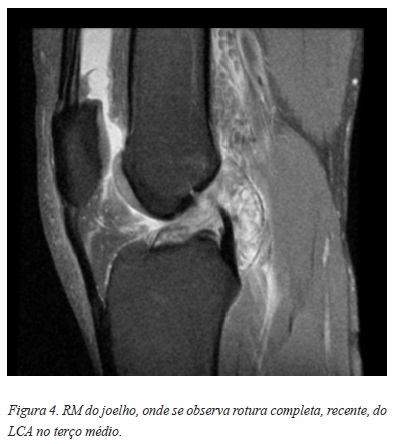

A TAC é utilizada na impossibilidade de realizar a RM, pois a RM permite uma melhor visualização dos ligamentos, cartilagem e dos outros componentes do joelho. A RM é pois muito útil no pré-operatório, pois indica o tipo e a gravidade da lesão (Figura 4).13,14